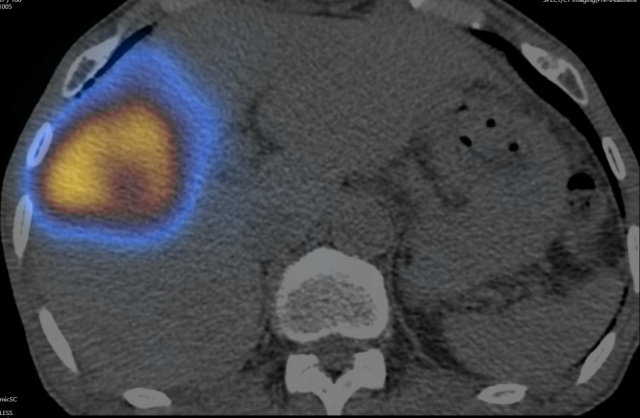

图:患者术后SPECT/CT显像,核素在病灶区沉积良好

由由疾控感控办公室协助,全面做好接诊空间、疫情防控和消杀部署,核医学科、放射科、钇90中心导管室、留观室、肝胆胰中心医护团队严密防护,经约4小时,患者钇[90Y]微球介入治疗手术顺利完成。术后SPECT/CT显示病灶部位微球浓聚良好,无肝外微球异常浓聚,患者肝功正常,术后第二日顺利出院。(编辑  韩冬野